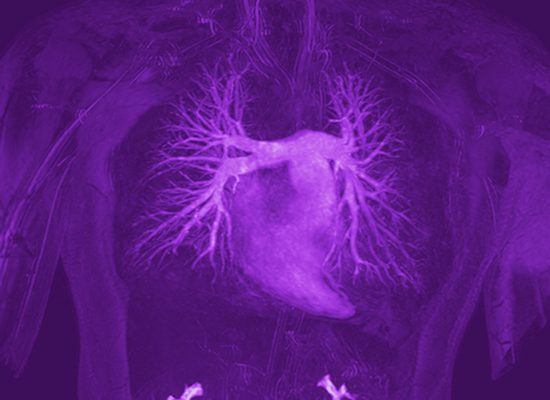

001 Darstellung der Pulmonalarterien

004 Lungenvenen